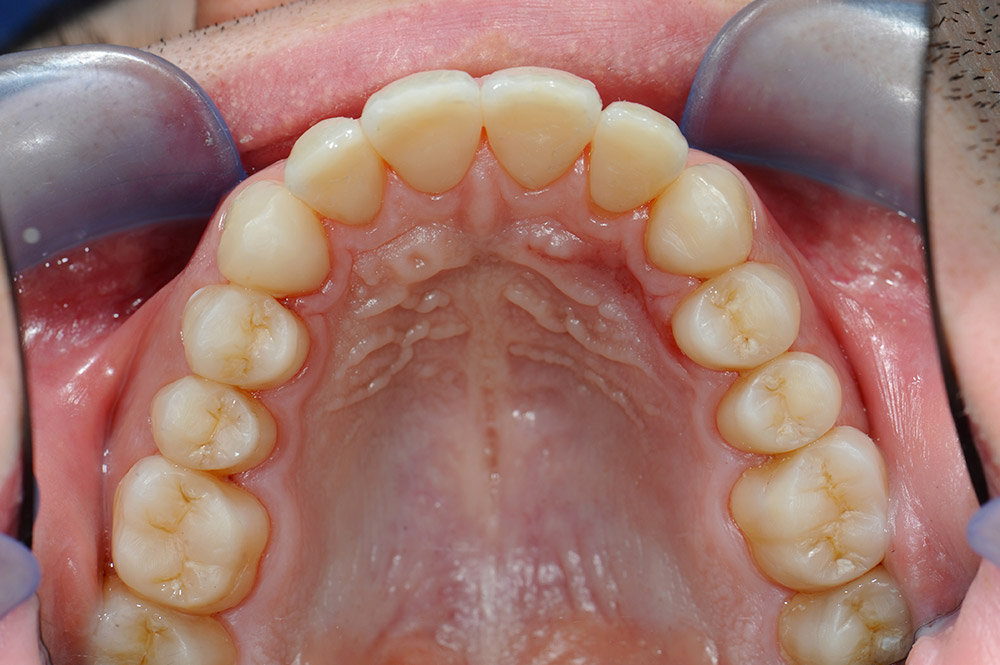

Corone in composito Luna Wing metal free e intarsi in composito

Il caso si presentava semplice, il paziente desiderava riabilitare solamente i 4 incisivi centrali superiori allungandoli per ripristinare una corretta prporzione.

Ma avendo perso anche dimensione verticale non si potevano allungare senza un rialzo di masticazione, a causa della funzione protrusiva.

Per motivi prevalentemente economici si è optato per una serie di intarsi in composito e corone a giacca in composito sui quattro incisivi superiori.